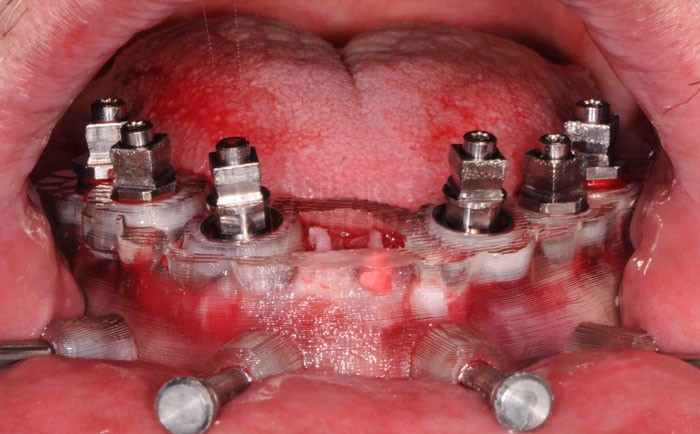

Dima chirurgica inf. posizionata in cavità orale